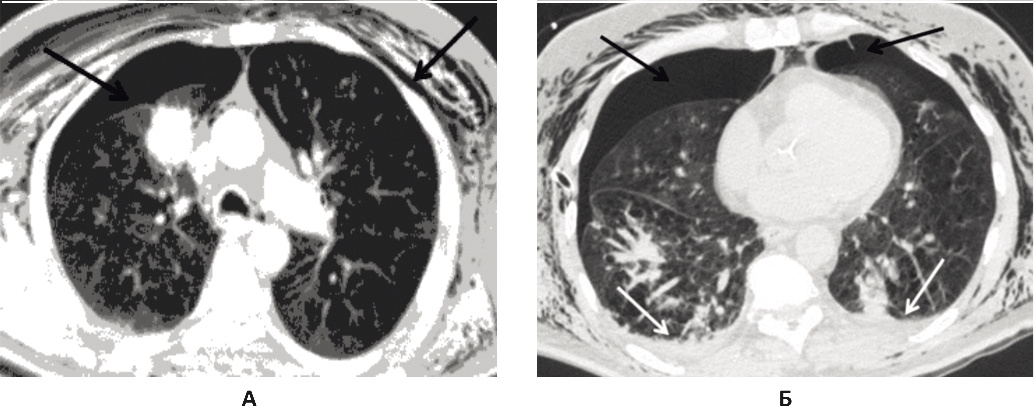

12.02.2017 г. состояние пациента стабильно тяжелое. На контрольной КТ грудной клетки отмечена положительная динамика. Слева легкое полностью расправилось, справа же сохранялся малый пневмоторакс. Сохранявшаяся межмышечная и подкожная эмфизема грудной клетки в динамике значительно уменьшилась. В базальных отделах легких стали заметны компрессионные и воспалительные изменения (рис. 4).

Рис. 4. КТ грудной клетки через 13 дней после поступления, состояние после дренирования правой и левой плевральных полостей. А: в плевральных полостях, в мягких тканях грудной клетки, в средостении сохраняется свободный воздух, справа количество воздуха наросло, слева значительно уменьшилось, пневмоторакс слева незначительно выражен в базальных отделах (черные стрелки); Б: сохраняются небольшое количество жидкости в плевральных полостях и компрессионные изменения в базальных отделах обоих легких (белая стрелка)

По дренажам плевральных полостей продолжался сброс воздуха: слева слабо выраженный, справа массивный. Было решено, учитывая положительную динамику, продолжать интенсивную терапию, активную аспирацию по плевральным дренажам, с тем чтобы, достигнув окончательной герметизации легочной паренхимы слева, выполнить бронхографию с последующей эндоблокацией бронха, являющегося источником бронхоплеврального свища справа. В целях создания условий для скорейшего закрытия бронхоплевральных свищей предпринято наложение малого пневмоперитонеума в объеме 800 мл, через параумбиликальный доступ, иглой Вереша, под местной анестезией. Пациент вертикализирован. Через два часа после наложения пневмоперитонеума сброс воздуха по плевральному дренажу слева полностью прекратился, наступил герметизм левой плевральной полости. По дренажу правой плевральной полости продолжался сброс воздуха.